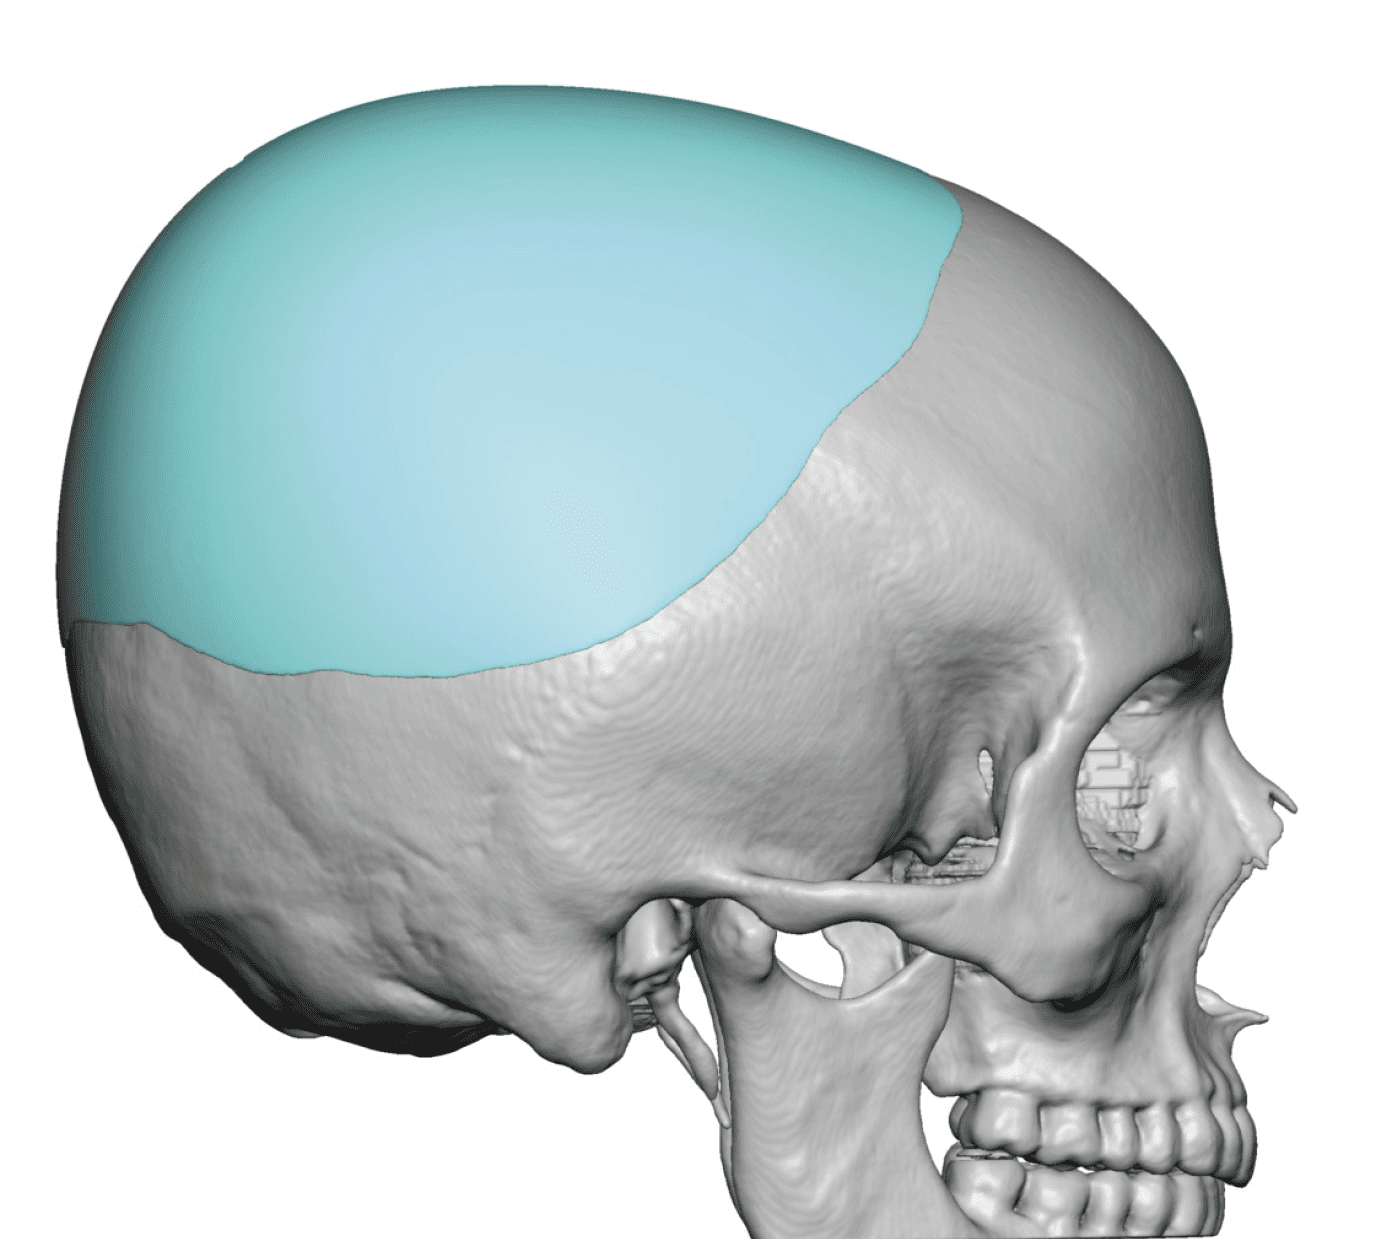

Placement of custom extended forehead-temporal implants through incisions in the crease behind the ear. (he had a prior back of head skull implant which is green in the implant designs and which the head widening implants partially covered it)

Desire for change of head shape from front view form an inverted V shape to a rounder and wider head shape.

Placement of custom extended forehead-temporal implants through incisions in the crease behind the ear. (he had a prior back of head skull implant which is green in the implant designs and which the head widening implants partially covered it)